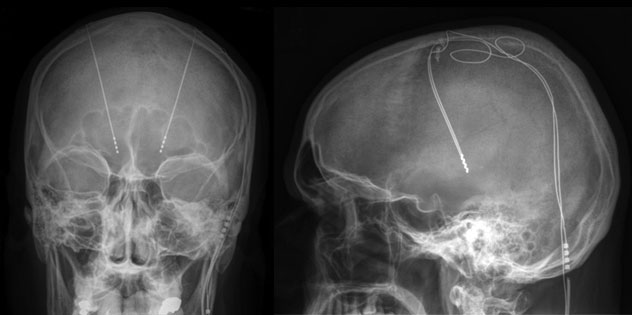

Deep brain stimulation

Deep brain stimulation involves putting electrodes deep within the brain. The impulses from the electrodes help the body manage the brain activity that causes seizures. The electrodes attach to a pacemakerlike device placed under the skin of the chest. The device manages how much stimulation happens.

MRI of deep brain stimulation

A magnetic resonance imaging (MRI) scan of deep brain stimulation shows the location of electrodes placed in the brain.

- Deep brain stimulation. In deep brain stimulation, surgeons implant electrodes into a specific part of the brain, typically the thalamus. The electrodes are connected to a generator implanted in the chest. The generator regularly sends electrical pulses to the brain at timed intervals and may reduce seizures. Deep brain stimulation is often used for people whose seizures don't get better with medicine.